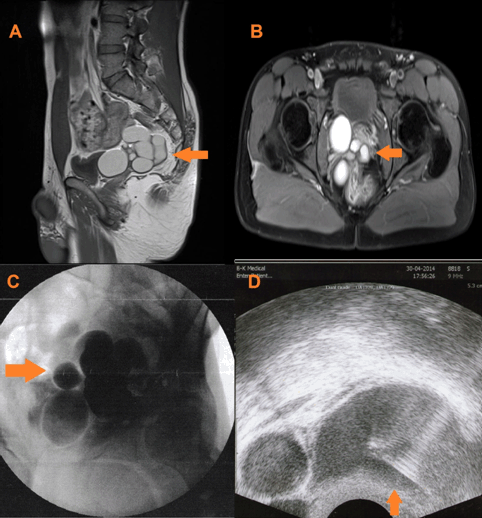

A 27-year-old, married male who has two children, was referred to our clinic for difficulty in urination, frequent urination and pain in pelvic area. Lack of right kidney and multilocular cystic lesion with a diameter of 70x84 mm in the lateral pelvic area neighboring rectum was reported in USG and abdomen CT in the hospital from where he referred to us. Genitourinary system was normal on physical examination. Soft cystic mass with unclear borders was palpated on rectal exam. Urinary examination and culture were normal. Right kidney was not detected on the urinary system ultrasound. Left kidney and bladder were normal. Transrectal ultrasound and pelvic MRI scan was done. Cystic dilatations were observed in the right seminal vesicle in pelvic MRI scan and the biggest of them had a diameter of 70x60 mm (Figure 1). It was pressing on the bladder and rectum. Same results were confirmed in the transrectal ultrasound (Figure 1). Puncture was made inside the cyst. Dark brown liquid was aspirated. Plenty of spermium cells were observed in the fluid. Malignant cells were not detected cytology. Contrast material was given inside the cyst in transrectal ultrasound (TRUSG) and examined in fluoroscopy. No connection with the other seminal vesicle was observed. Retrograde contrast material exit from pelvic area to the abdomen and bladder was not observed. Cystoscopy was done for the patient. Cyst pressure was observed on right side wall of the bladder. Right side ureteric orifice was not observed. Open operation under general anesthesia was made since we could not completely explain pathogenesis. During the operation it was observed that ureter and rudimentary kidney opened to the cyst. Nephroureterectomy and cyst excision was done (Figure 2). Patient’s drain was taken out on the third day since the patient did not have any postoperative complaints. The patient was discharged on the fifth day. The result of the pathology demonstrated lobular disorganization in the small kidney with primitive collecting ducts embedded in connective tissue and seminal vesicle.

Figure 1: (A, B) Right seminal vesicle cyst on MRI scan (oblique and transvers sections), (C) Transrectal ultrasound guide has given contrast agent into the cyst (retrograde cystography), (D) Cyst with a needle puncture through TRUSG.